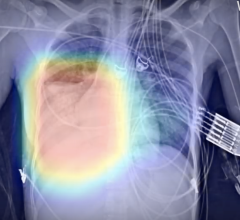

August 7, 2020 — Rapid first aid during cardiac arrest makes the difference between life and death. But what happens to ...